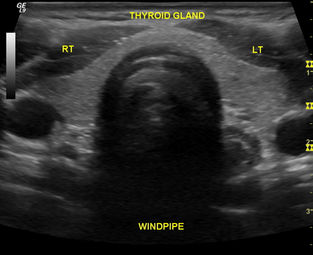

RENAL ULTRASOUND - YouTube

Ultrasound Protocol of the Kidneys ... View Video

How To: Kidney Ultrasound Exam - YouTube

Visit http://www.sonosite.com/education/ Learn to examine the kidneys with ultrasound. Topics covered include patient position, probe position, landmarks, an ... View Video